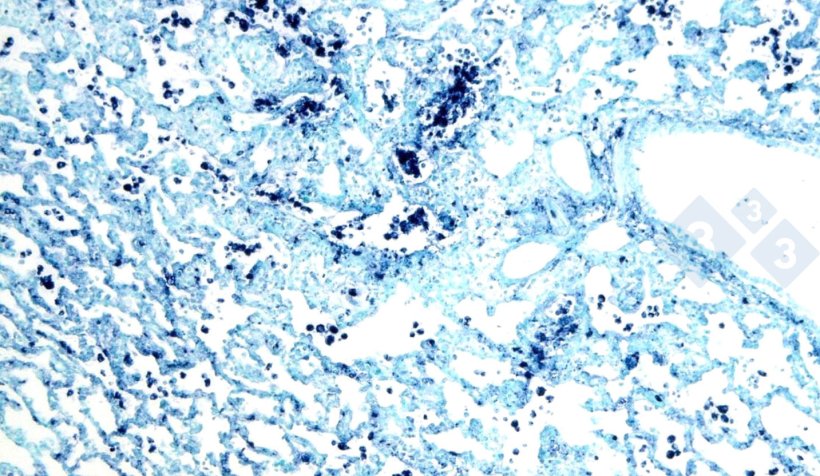

As mais utilizadas são a imunohistoquímica (Figura 3) e a hibridização in situ (Figura 4), que permitem a detecção de agentes patogénicos no local de acção, apoiando o seu papel no contexto clínico e patológico. Além disso, existem outras técnicas (colorações histoquímicas), que não são suficientes para estabelecer uma etiologia específica, mas podem fornecer pistas sobre a causa (por exemplo, coloração de Groccot para fungos ou coloração de Gram para bactérias gram-positivas ou gram-negativas).

Figura 4. Hibridação in situ para detectar circovirus suíno 2 (PCV2) num pulmão afectado de pneumonia intersticial.